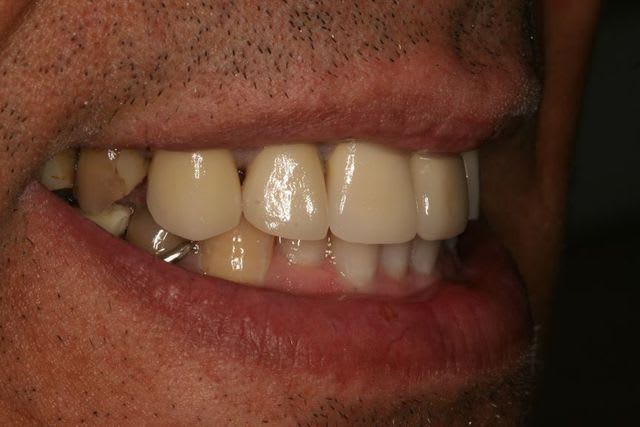

Tiens ça tombe bien j'ai un cas là.

Le patient vient me voir comme ça, il a les droits CMU ouverts, à jour et vient à ses RDV.

La solution pour moi :

Extraction 24 37

endo 12 -> 22, 17 47

CCM 13 -> 22

CC 17 47

Meulage occlusal 35

2 stellites

- Est ce que ce plan de traitement respecte la NGAP ? En particulier au niveau antérieur (traitement endo et CCM) ? Que feriez vous ?